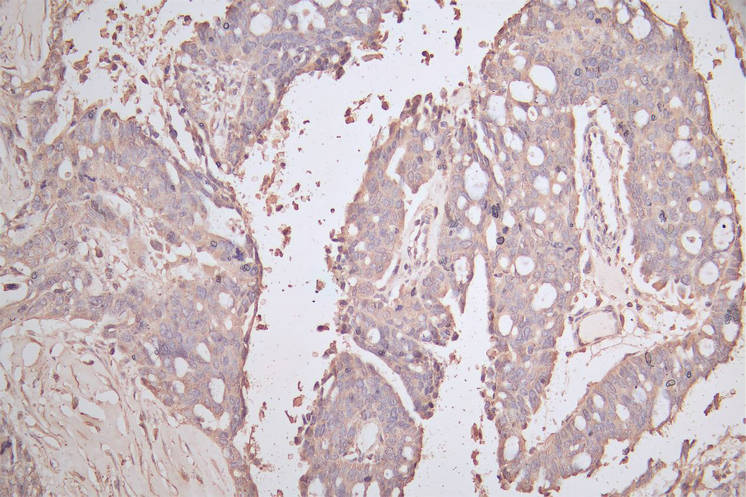

CDH1 Recombinant Monoclonal Antibody; CSB-RA005034MA1HU

CDH1 Recombinant Monoclonal Antibody

CSB-RA576116A0HU

CSB-RA005034MA2HU